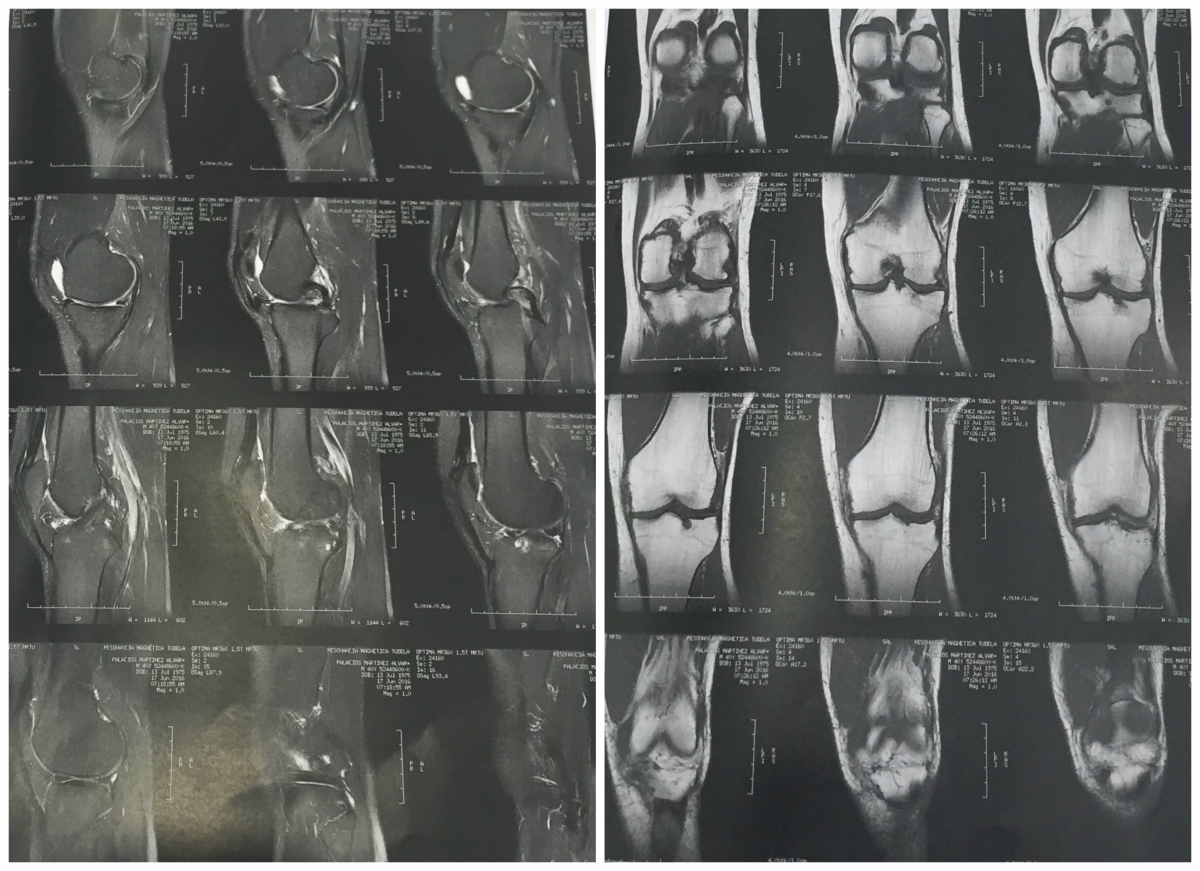

A las consultas de Podoactiva acude un deportista por molestias en la zona interna de la rodilla. Después de realizar una resonancia magnética el médico traumatólogo se le diagnostica meniscopatía interna.

La meniscopatía es una lesión producida en los meniscos de la rodilla desarrollada por factores degenerativos o traumáticos.